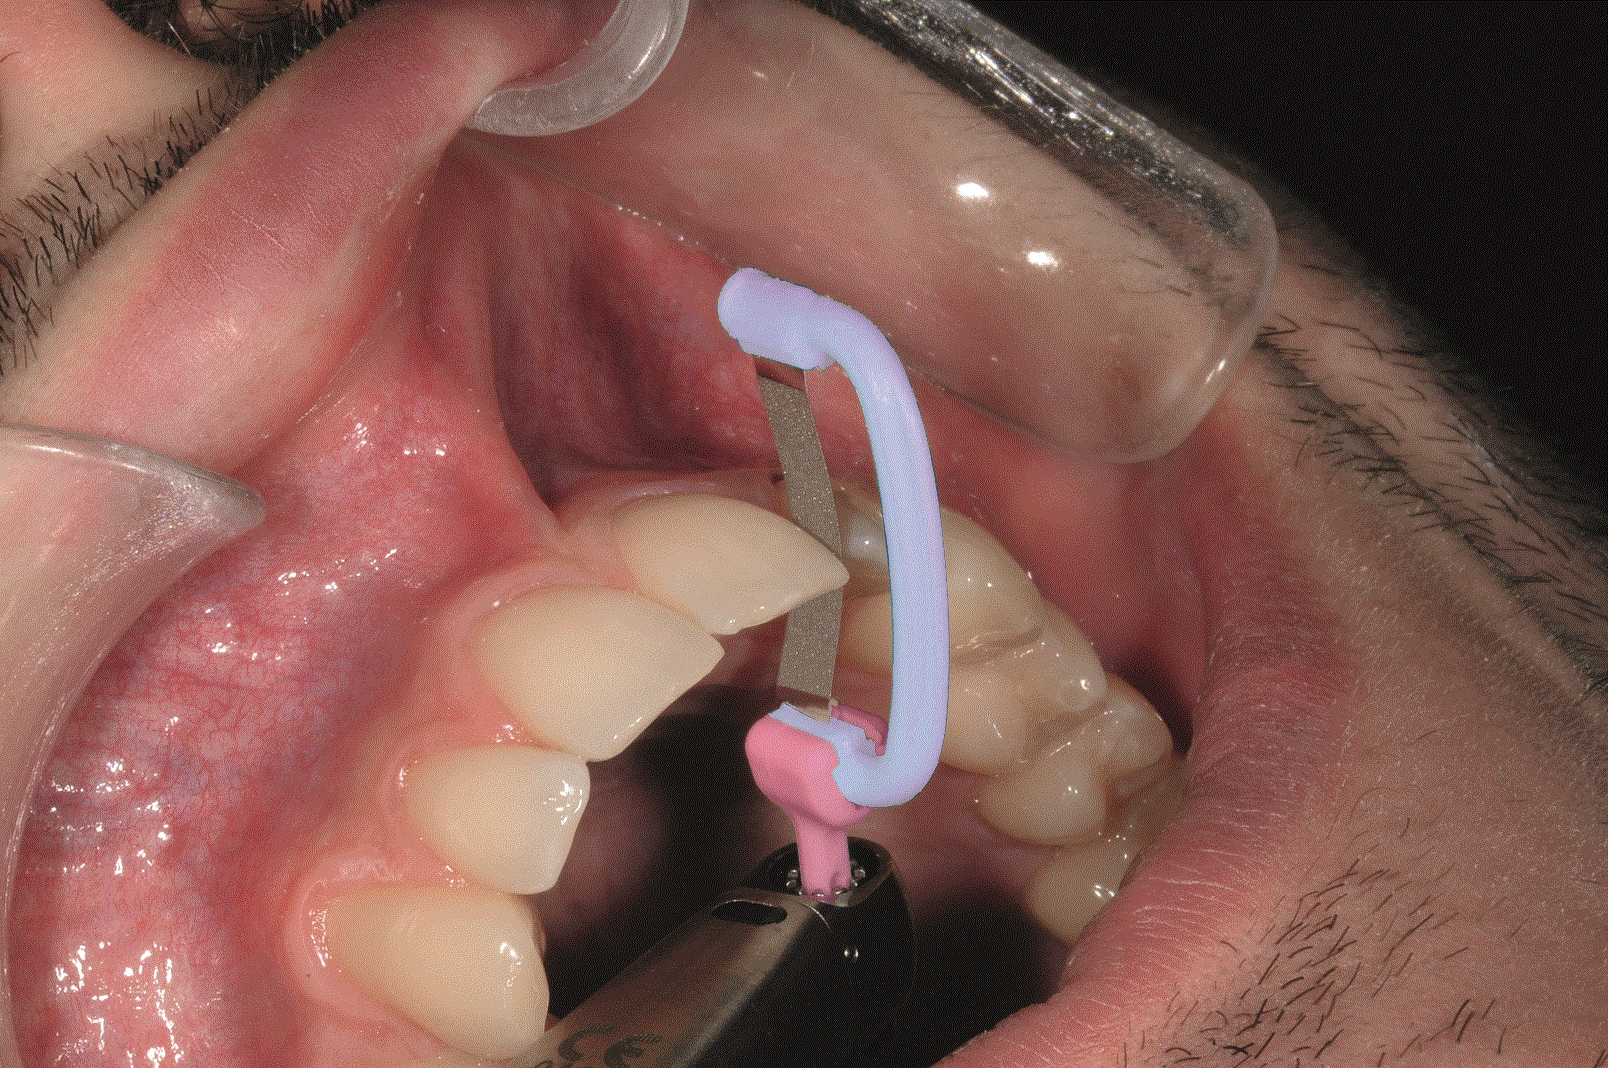

Limes de stripping G5-PROLIGN

Description

- Morbi in sem quis dui placerat ornare. Pellentesque odio nisi, euismod in, pharetra a, ultricies in, diam. Sed arcu. Cras consequat.

- Praesent dapibus, neque id cursus faucibus, tortor neque egestas augue, eu vulputate magna eros eu erat. Aliquam erat volutpat. Nam dui mi, tincidunt quis, accumsan porttitor, facilisis luctus, metus.